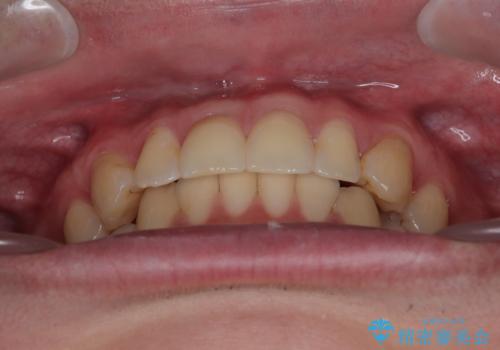

- 前歯のデコボコと突出感を気にして来院された患者様です。

極力目立たない装置を希望とのことで、インビザラインを用いて非抜歯で矯正治療を行うこととしました。

事前に親知らず4本を抜歯し、多少歯列を後方に移動できるように準備をした上で、なるべく歯と歯の間を削ることなくデコボコを解消できるように計画しました。

お仕事が忙しく、1日の装着時間は不十分となる日もありましたが、治療は順調に進めていくことができました。

途中、以前大きなむし歯で処置をした歯が痛み出し、根管治療が必要となったため、根管治療とオールセラミッククラウンによる補綴治療を行い、その後にインビザラインによる仕上げの歯列移動を行い、無事に治療を終えることができました。